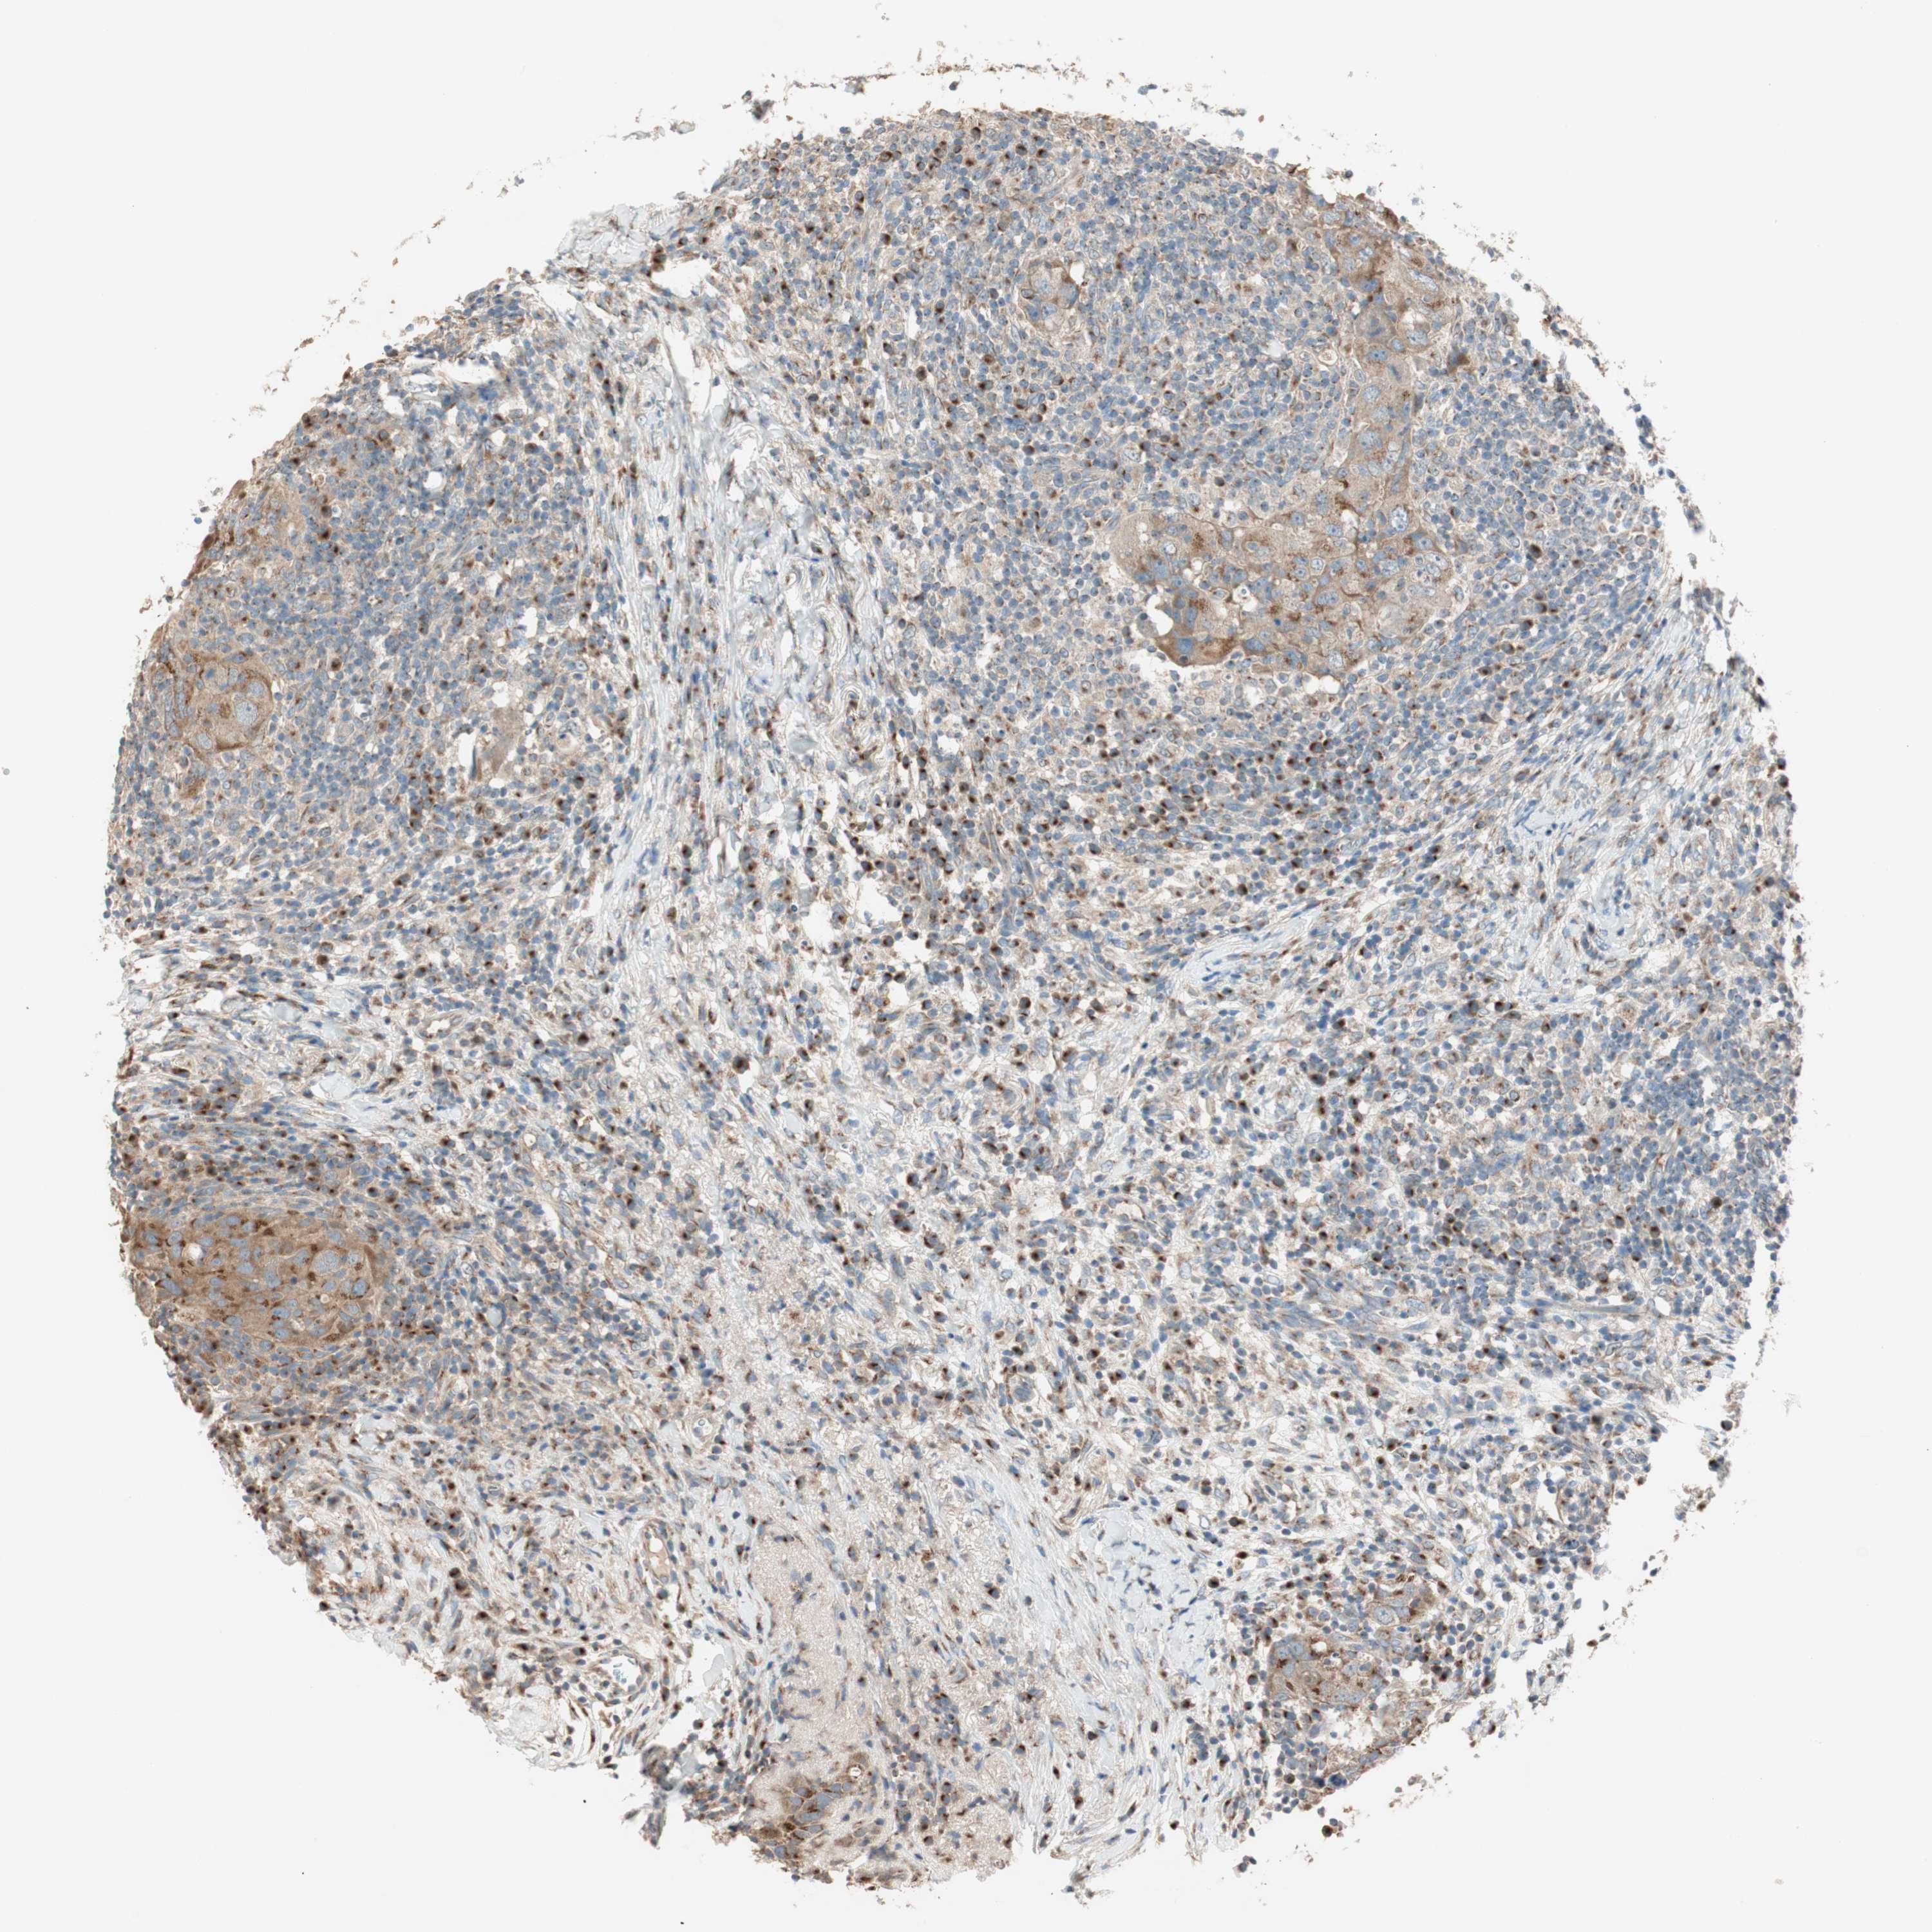

BRCA TCGA BRCA VALIDATION PROTEIN EXPRESSION

ANTIBODIES

AND

VALIDATION